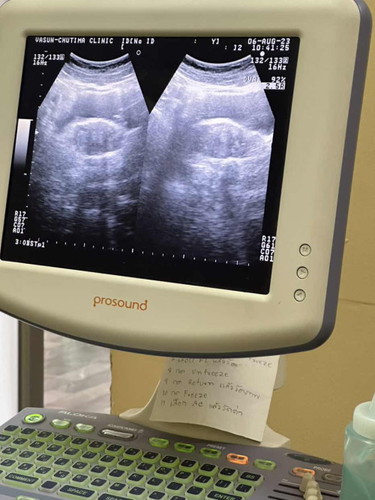

ตรวจขึ้น2ขีด แต่ไปซาวไม่เจอถุงตั้งครรภ์🥹

ตรวจขึ้น2ขีดประจำเดือนขาด9วัน ไปซาวหมอบอกว่ายังไม่เจอถุงตั้งครรภ์ คุณหมอบอกว่าตั้งครรภ์ยังอ่อนมากๆ ตอนนี้กังวลมากค่ะ🥹🥹🥹

ของเราตรวจก่อนประจำเดือนจะมา2วันค่ะ คือฝันแล้วก็มีอาการแปลกๆเหมือนตอนท้องลูกคนแรก ขึ้นสองขีดชัดเลย ไปคลีนิคหมอก็ยังไม่ให้ฝากนะคะเจอแค่ถุงตั้งครรภ์ หมอให้รอเจอตัวน้องก่อนถึงจะถือว่าเป็นการตั้งครรภ์สมบูรณ์

เรา ปจด. เดือนขาดไป 3 วันตรวจขึ้น 2 ขีด รีบไปหาหมอเจอแค่ถุงตั้งครรภ์ตอน 4 สัปดาห์ ยังไม่เจอตัวน้อง พอได้ 7 สัปดาห์ไปซาวน์ใหม่ค่อยเจอตัวน้องค่ะ ตอนนี้ 6 เดือนแล้ว แม่ใจเย็นๆน๊า เดี๋ยวก็เจอน้อง